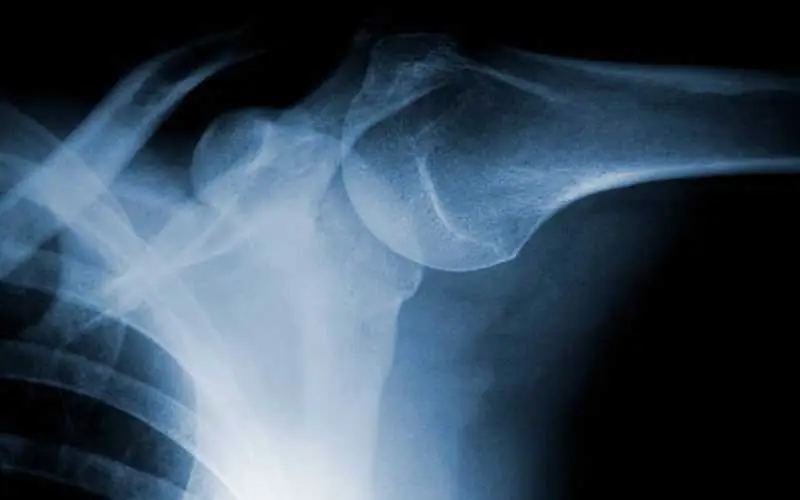

Teşhis sürecinde öncelikle hastanın hikayesi dinlenir ve fizik muayene yapılır. Ardından kireçlenmenin derecesini belirlemek için radyolojik incelemeler (röntgen, MR) kullanılır. Doktor; hastanın yaşı, şikayet süresi, mesleği ve fiziksel aktivite düzeyine göre tedavi planını şekillendirir.